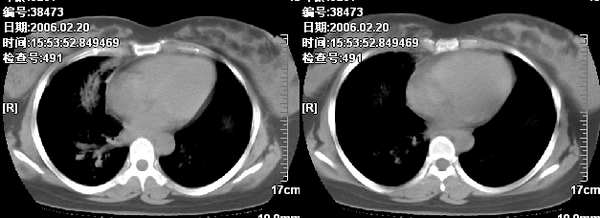

为便于观察,帮战友把图象搬过来。

我觉得不能排除肺段炎症,建议近期治疗复查。

右肺上叶前段与中叶见较大团块影。边界较清晰,纵隔隆突前淋巴结增大。考虑1肺部间叶组织肿瘤可能。2感染性病变

我觉得不要把患者年龄作为轻易排除肺癌的依据,病变呈大块状软组织密度,右肺中叶支气管可见中断,右侧肺门增大,要高度警惕肺癌,支气管镜应该能够给出正确的诊断。间质来源的恶性肿瘤尽管可以考虑到,但是从发病率上来说不首先考虑。

已经手术结果为淋巴瘤

补充病例结果是:肺间变大t细胞淋巴瘤. 非霍奇金淋巴瘤(间变大t细胞性)iv期bipi 2分

右肺中下叶切除